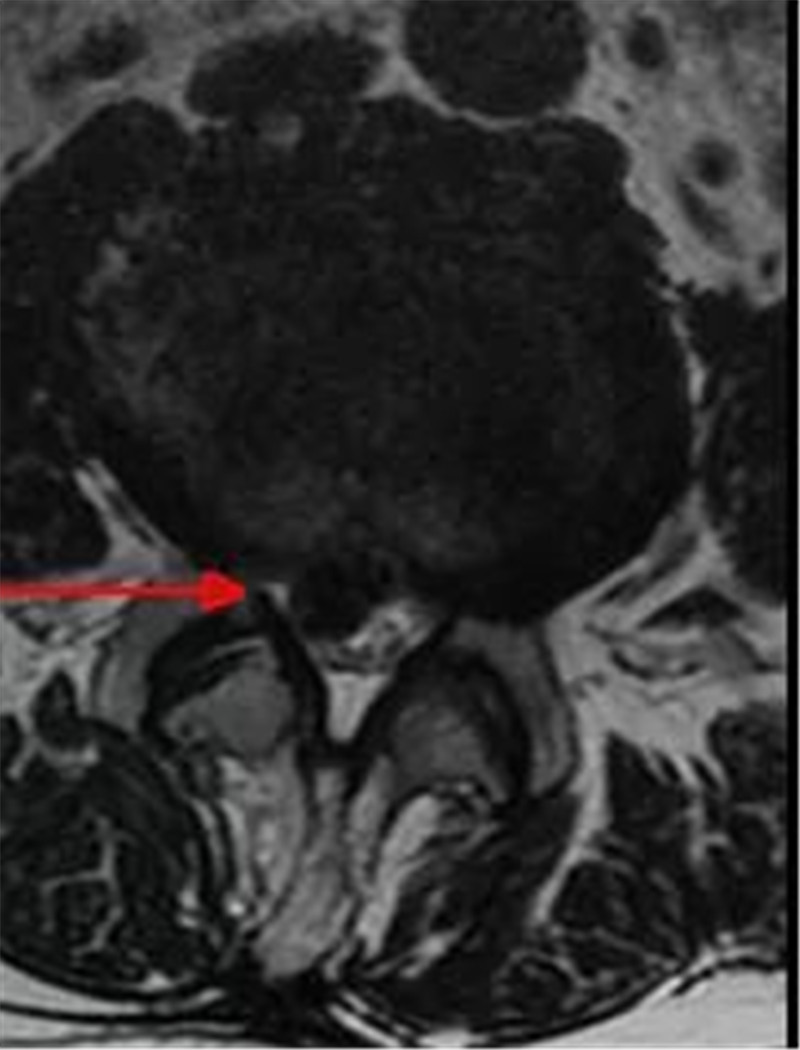

25岁男子玩游戏时突发脑出血,医生做了2次手术才救回了他

近日,一25岁年轻男子王先生玩游戏时突发脑出血,病情急剧恶化,仅一小时便瞳孔放大!三水区人民医院紧急开通绿色通道,卒中中心神经外科团队先用3小时手术清除血肿和脑部减压,保住其生命;术后第三天,王先生情况好转,医生再用3小时成功为其实施全脑血...